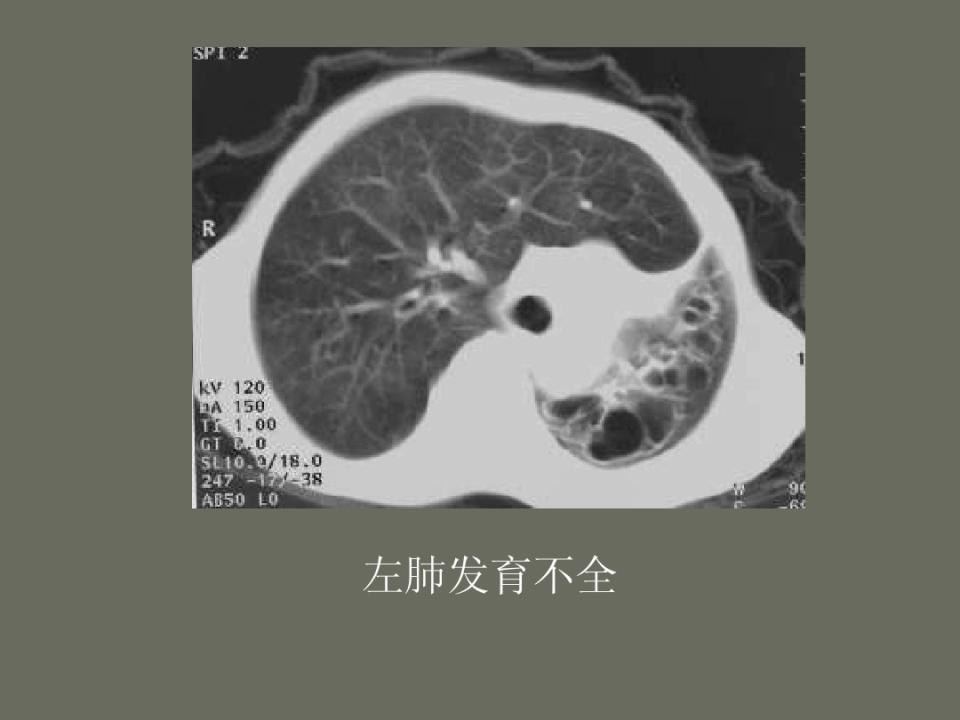

肺部先天性疾病的影像诊断